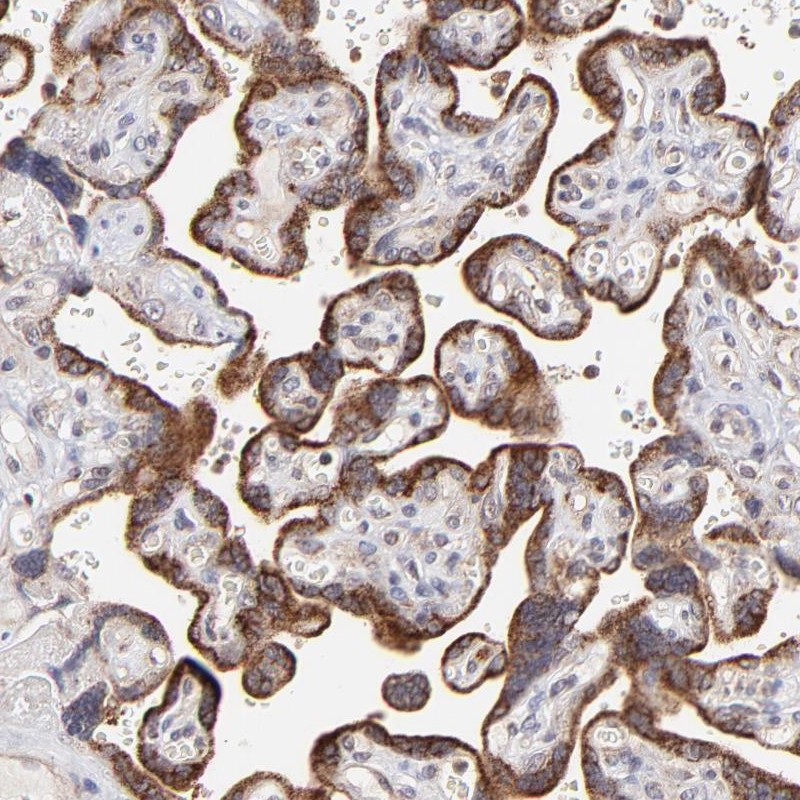

Immunohistochemical staining of human placenta shows strong cytoplasmic positivity in trophoblastic cells.